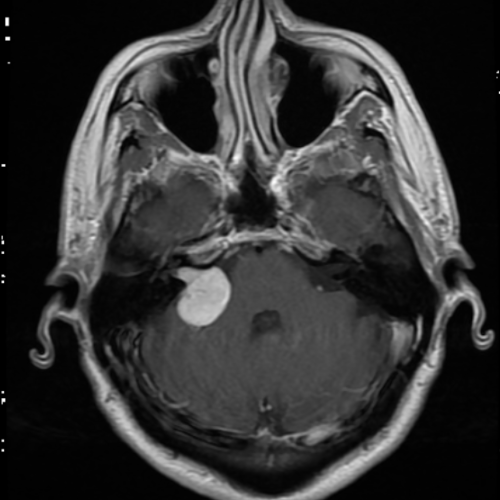

Neuro Fellowship

Reviews of neuro topics with clinical pearls, differentials, and in-depth discussions.

131 cases  13.1 CME

Brain Tumors

105 cases

Neuro Courses

Includes our call preparation neuro courses (Neuro CT and Neuro MRI) and our neuro fellowship courses.